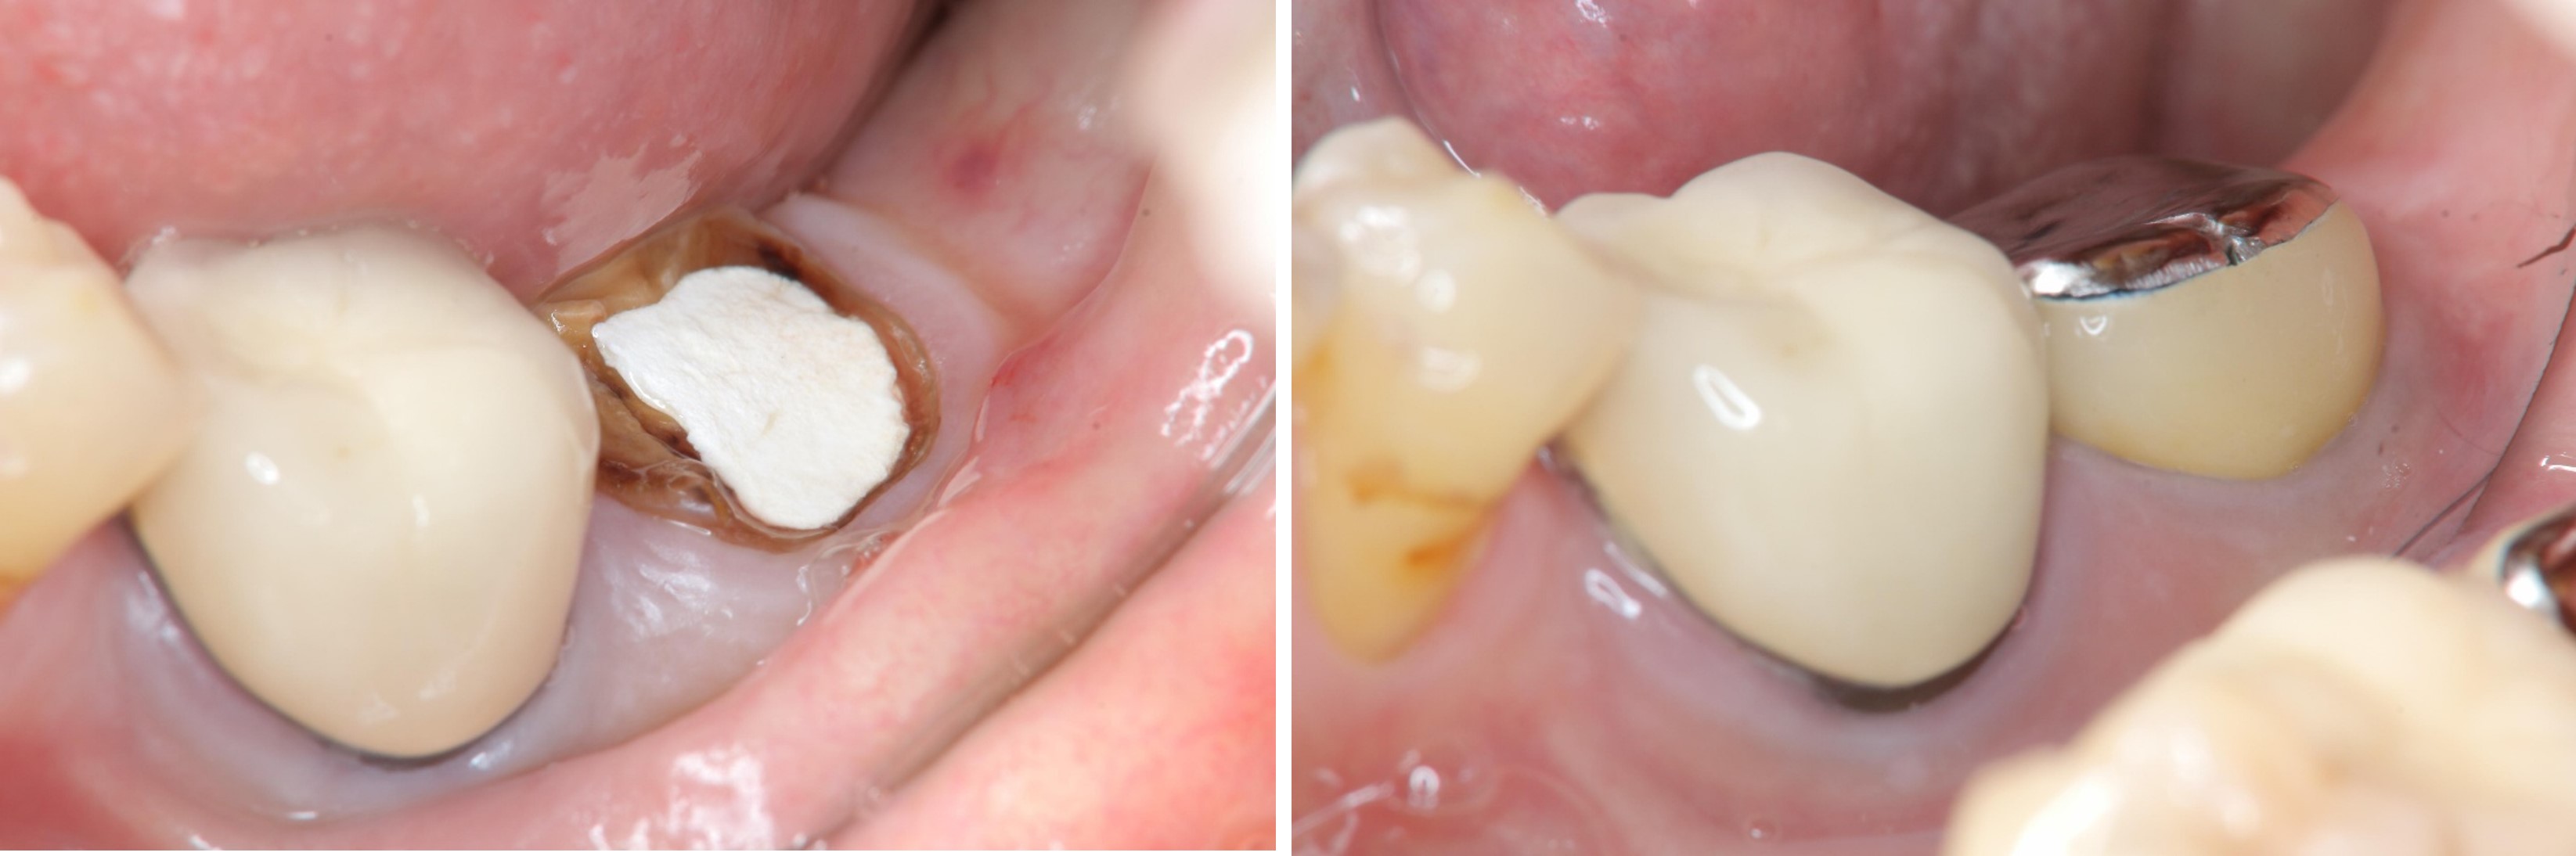

術前、術後比較

當牙齒齲齒部分過大或是牙齒大面積斷裂,導致臨床牙冠邊緣靠近牙齦或甚至在牙齦之下,表示臨床牙冠太短,不足以製作假牙。此時應當先執行牙冠增長術,來爭取更長的臨床牙冠以得到足夠的圍箍效應,假牙才不容易脫落。如不先執行牙冠增長術就貿然做上假牙,將造成牙齒的圍箍效應不足,假牙受力後容易脫落甚至整顆牙齒斷裂,以至於面臨需要將牙齒拔除的結果。

因為齲齒或牙冠斷裂至牙齦下方,導致齒質不足、牙冠過短,以致無法有足夠的生物寬度或是圍箍效應,此為臨床上需要執行牙冠增長術的最常見原因。